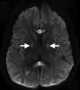

Hypoxic-ischemic encephalopathy

Cerebral hypoxia is a form of hypoxia (reduced supply of oxygen), specifically involving the brain; when the brain is completely deprived of oxygen, it is called cerebral anoxia. There are four categories of cerebral hypoxia; they are, in order of severity: diffuse cerebral hypoxia (DCH), focal cerebral ischemia, cerebral infarction, and global cerebral ischemia. [Source: Wikipedia ]